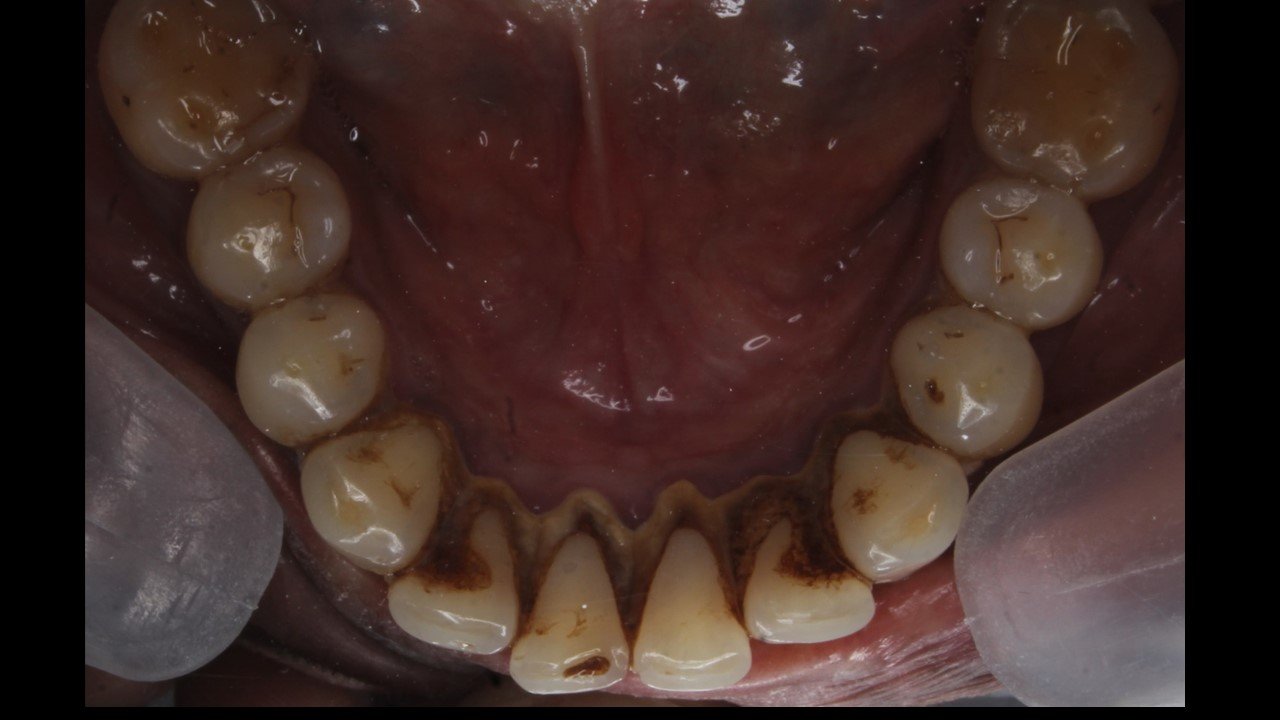

Case 1